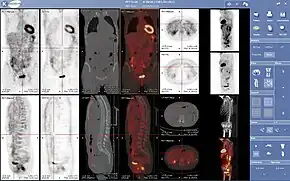

Complete body PET-CT fusion image

PET scans are increasingly read alongside CT or MRI scans, with the combination (co-registration) giving both anatomic and metabolic information (i.e., what the structure is, and what it is doing biochemically). Because PET imaging is most useful in combination with anatomical imaging, such as CT, modern PET scanners are now available with integrated high-end multi-detector-row CT scanners (PET-CT). Because the two scans can be performed in immediate sequence during the same session, with the patient not changing position between the two types of scans, the two sets of images are more precisely registered, so that areas of abnormality on the PET imaging can be more perfectly correlated with anatomy on the CT images. This is very useful in showing detailed views of moving organs or structures with higher anatomical variation, which is more common outside the brain.